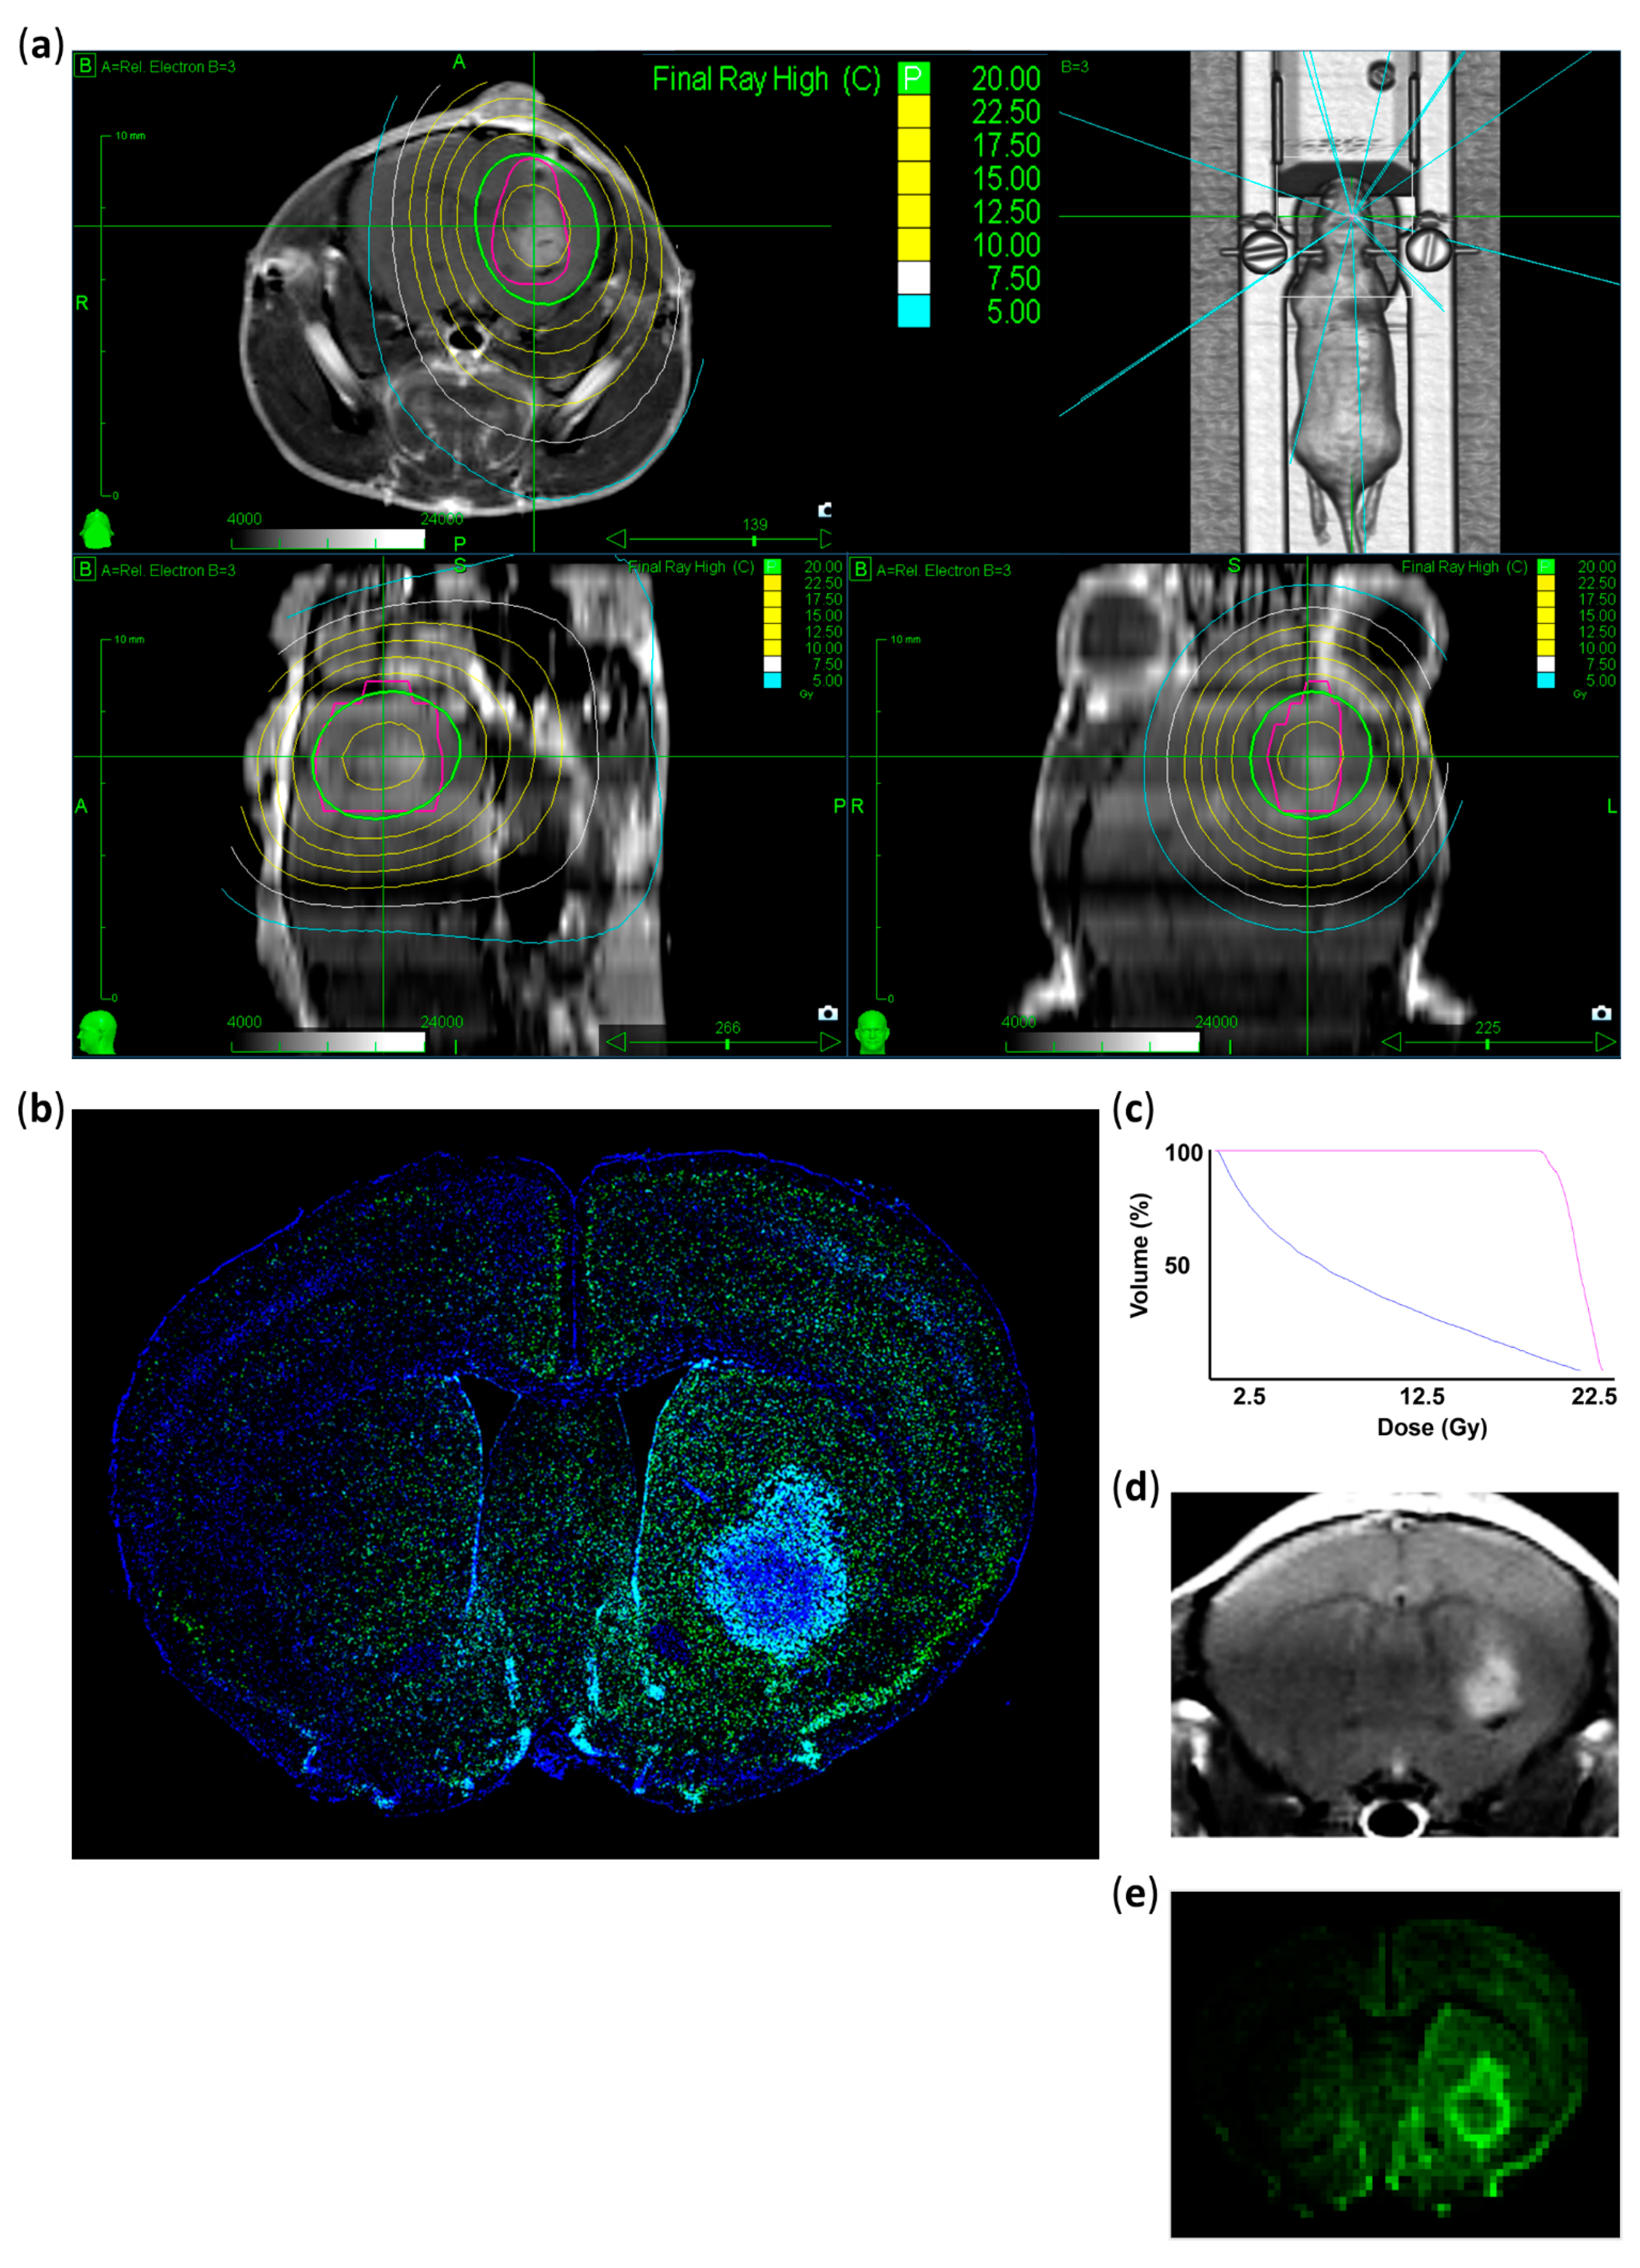

2.5. CyberKnife Irradiation

3.1. Verification of the Irradiated Area